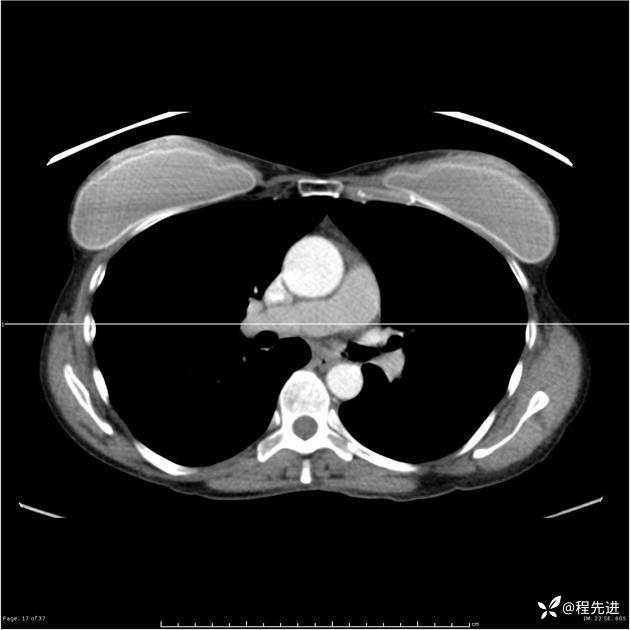

病例女,53岁,气管、左主支气管、下叶支气管内结节,乳头状瘤?期待你的精彩解读

女,53岁

乳头状瘤?